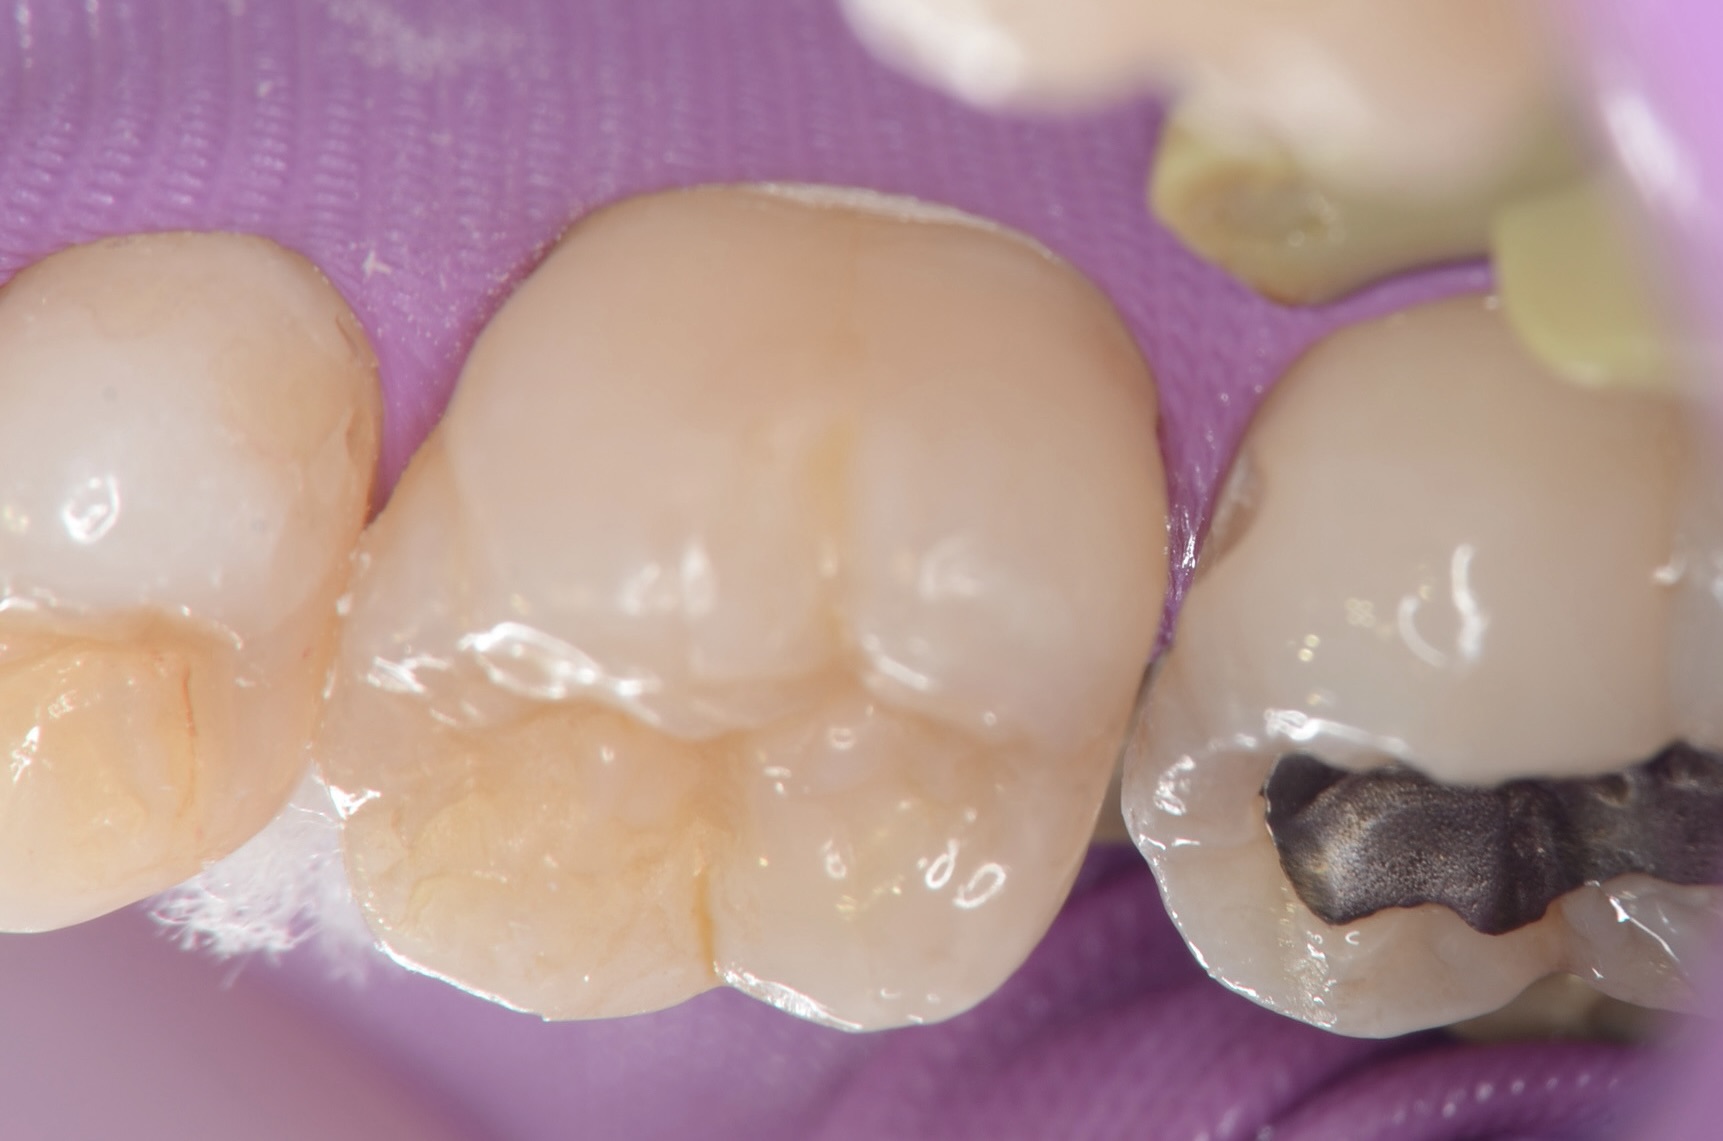

ラバーダム装着

7番のインレーを外します。 -

ダイレクトボンディング

象牙質の範囲まで、濃い目の色のレジンを充填します。中の色を濃くしておくと、最終的に僅かに透けて立体感が出ます。 -

充填完了

天然歯の形態を模倣して滑らかに仕上げました。 -